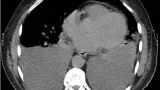

施設に入所中の超高齢患者さんが転倒して, 大腿骨顆上部を骨折して入院されていました.

AO/OTA分類では, 33A2.3でした.

骨折部にズレがないため, ギプス固定で治療する方針となっていました.